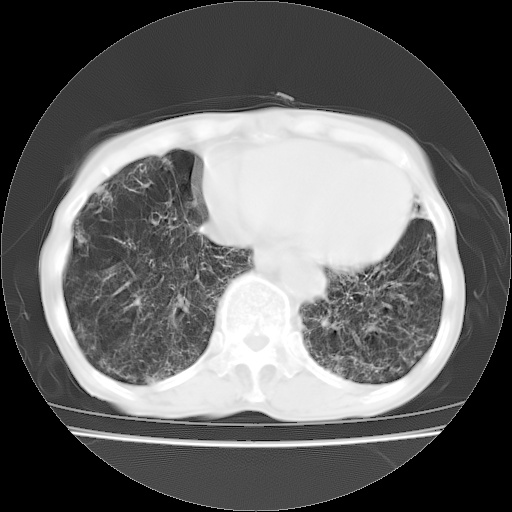

病人发热、气促就诊。原二周前已行ct扫描,当时诊断为双肺下叶、右肺中叶支气管扩张并感染,双肺上叶片状渗出性病变。今天复查胸部ct,双肺下叶支气管扩张并感染病灶较前明显吸收,但双肺上叶渗出性病变较范围较前明显增大。

现传今天ct图像给大家讨论。

肺内广泛感染并间质纤维化,牵拉性支气管扩张

双肺多发大片状、斑片状高密度渗出影,部分实变,考虑病毒性肺炎。